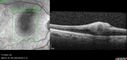

Pseudophakic CME chronic106 views74 year old man presented 14 weeks after cataract surgery with severe CME on topical therapy. Multiple attempts to taper drops failed. Also, the patient had a steroid responsive glaucoma. He ended up on BID PF, Ketorolac and Dorz/TimololNov 06, 2024